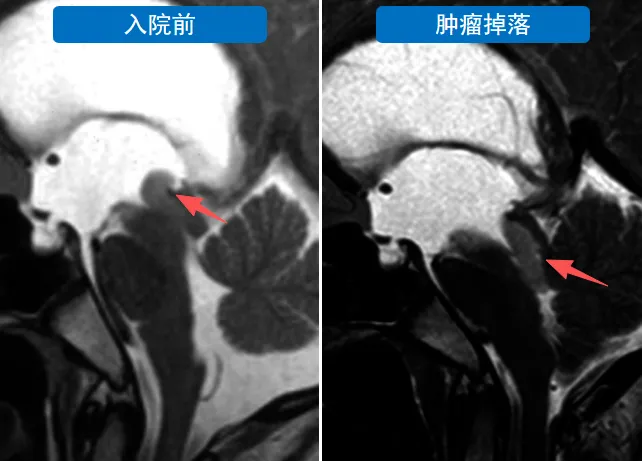

原来,导致里里病情突然恶化、危及生命的,仍是他脑中的那颗肿瘤。原本,肿瘤位于第三脑室后部的导水管入口处,虽然造成脑脊液循环受阻,但还没完全堵住这一通道。可是,就在几分钟前,这个带蒂的肿瘤太“贪玩”,竟直直地“溜”进了导水管,这下,中脑导水管被完全堵塞,里里也几乎在瞬间昏迷。

施罗德教授“快刀斩乱麻”,将肿瘤完整地切除并取出。此时没有了肿瘤这个“障碍物”,脑脊液通道也成功畅通无阻,无需再额外引流。手术结束,里里的状态明显好转,不再头痛呕吐,整个人有精神多了。肿瘤全切,里里没有出现任何神经功能缺损,几天后顺利出院。